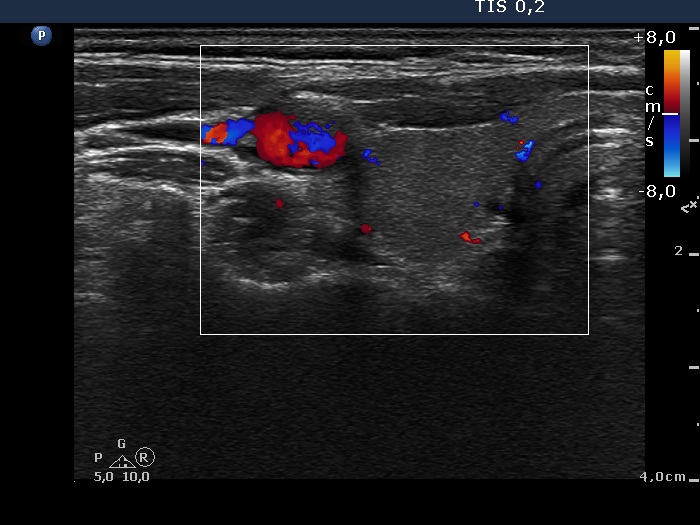

Lymph nodes in the neck - Case 1205 (ultrasonographic picture 3)

Right lobe, transverse scan, color Doppler mode. The vascularization is not specific.